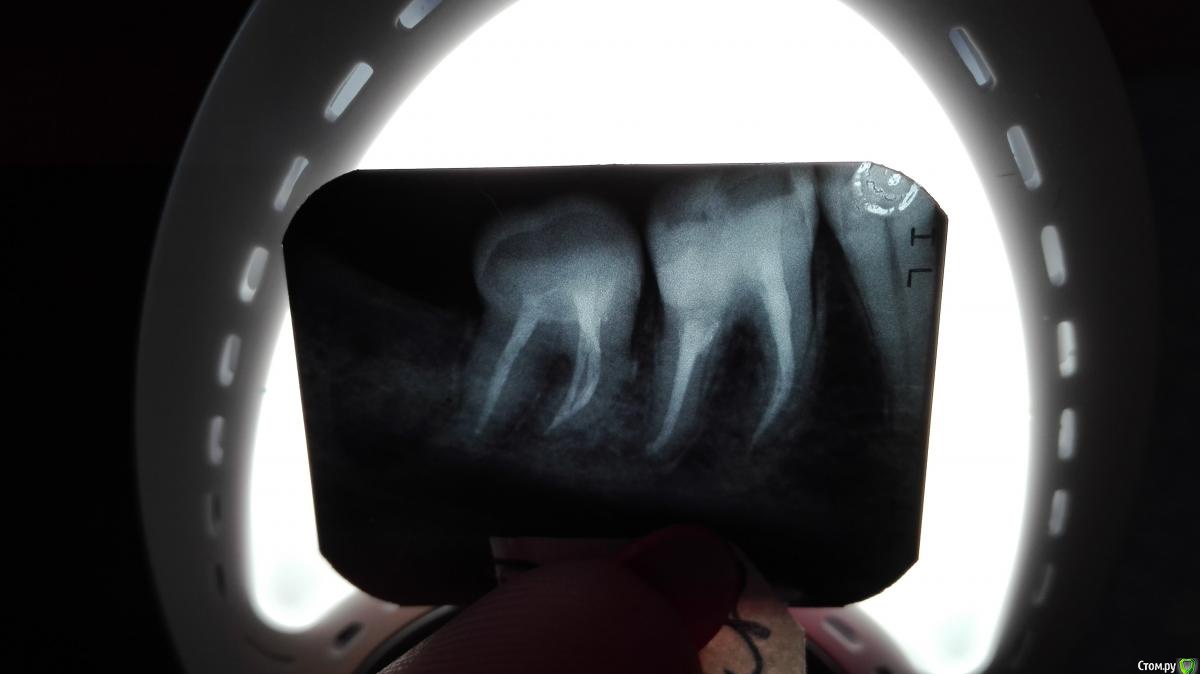

Вулкан Опубликовано 15 декабря, 2016 Автор Поделиться Опубликовано 15 декабря, 2016 (изменено) Эод. 15 зуб—4016зуб —20017зуб—40 44 зуб—545 зуб—646зуб—20047зуб— 200 мкa На оптг рынка спустя 3 месяца после удаления 48 Изменено 15 декабря, 2016 пользователем Вулкан Ссылка на комментарий